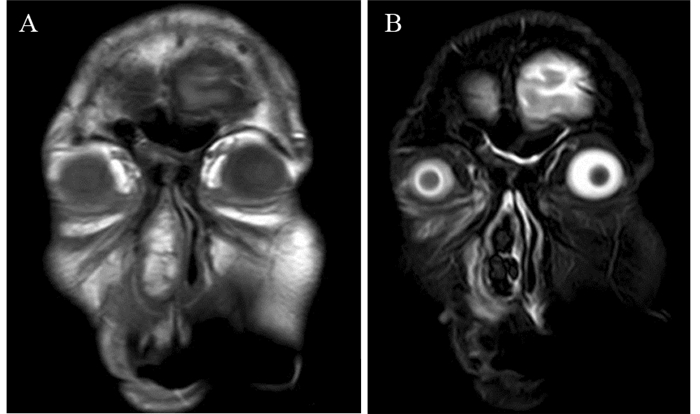

1 资料与方法 1.1 临床资料患者, 男, 59岁, 2016年5月1日以“右侧鼻腔新生物”收治于成都市第五人民医院。主诉:右侧鼻腔持续性鼻塞2年余, 加重伴脓涕、头昏痛2月。现病史:2年余前患者无明显诱因出现右侧鼻腔持续性鼻塞, 无脓涕及头昏痛等, 自服“感冒药”未见好转, 在当地医院就诊, 诊断为“右鼻息肉”, 建议手术治疗, 患者拒绝手术, 遂接受“丙酸氟替卡松鼻喷雾剂、通窍鼻炎颗粒”等保守治疗方案, 定期随访。2月余前患者自觉病情明显加重, 右侧鼻腔持续性鼻塞伴脓涕、嗅觉减退、无法通气, 同时伴间歇性头昏痛。不伴鼻出血及回吸涕带血, 无剧烈头痛伴恶心、呕吐, 无眼球运动受限及视力障碍或复视, 无面部异常隆起及感觉障碍等, 到我院就诊。一般查体:生命体征正常, 心肺腹(-); 专科查体:鼻外观稍饱满, 右侧鼻前庭见淡红色新生物, 包膜完整, 触诊实性、质地中等, 鼻腔及鼻咽部不能窥及, 左侧鼻腔未查见异常。纤维鼻咽喉镜检查:经左侧鼻腔查见鼻咽部正常; 右侧鼻腔见巨大淡红肉色新生物, 表面光滑, 包膜完整, 镜身无法进一步深入查探, 根蒂来源于中鼻甲内侧壁嗅区方向, 见图 1。鼻窦CT平扫:右侧鼻腔软组织密度影肿物, 边缘光滑, 境界清楚, 密度欠均匀, 邻近鼻腔外侧壁骨质压迫吸收变薄, 上颌窦、筛窦、蝶窦炎性积液, 鼻中隔不规则偏曲, 考虑右侧鼻腔良性肿物:血管瘤?鼻窦炎?见图 2。MRI检查:右侧鼻腔肿物, 充填鼻腔和鼻前庭, 最大径7.6 cm, 肿瘤根蒂部位于嗅区及鼻顶, T1WI显示以等信号为主, 肿块密度不均匀, T2WI显示高信号为主的混杂信号, 呈“三重信号征”, 颅内未见异常, 考虑倾向于右侧鼻腔恶性肿瘤, 见图 3。

| A: T1WI of MRI showed the lump was equisignal, and some high signals were also situated in it; B: hybrid signals showed in the lump which mainly presented high signals in T2WI of MRI, and the "triple signal sign" was obvious. 图 3 鼻窦MRI检查(冠状面) Figure 3 MRI findings of sinuses (coronal plane) |